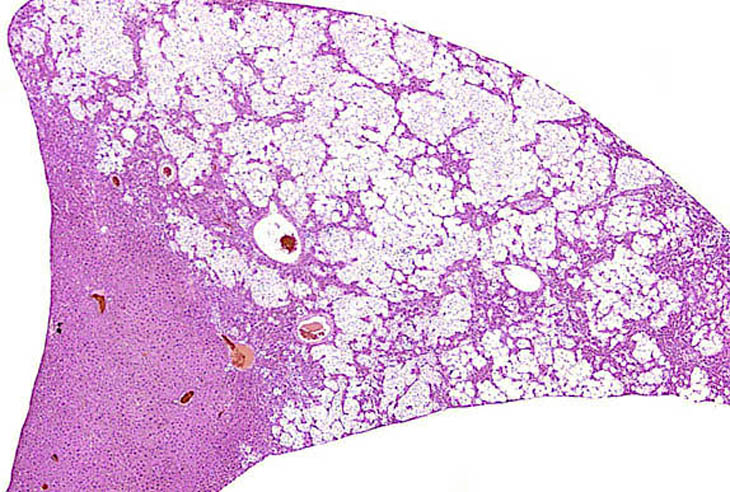

A relative discrete Ito cell tumor is present within this hepatic lobe; a higher magnification shows proliferation of stellate cells within the hepatic sinusoidal spaces.